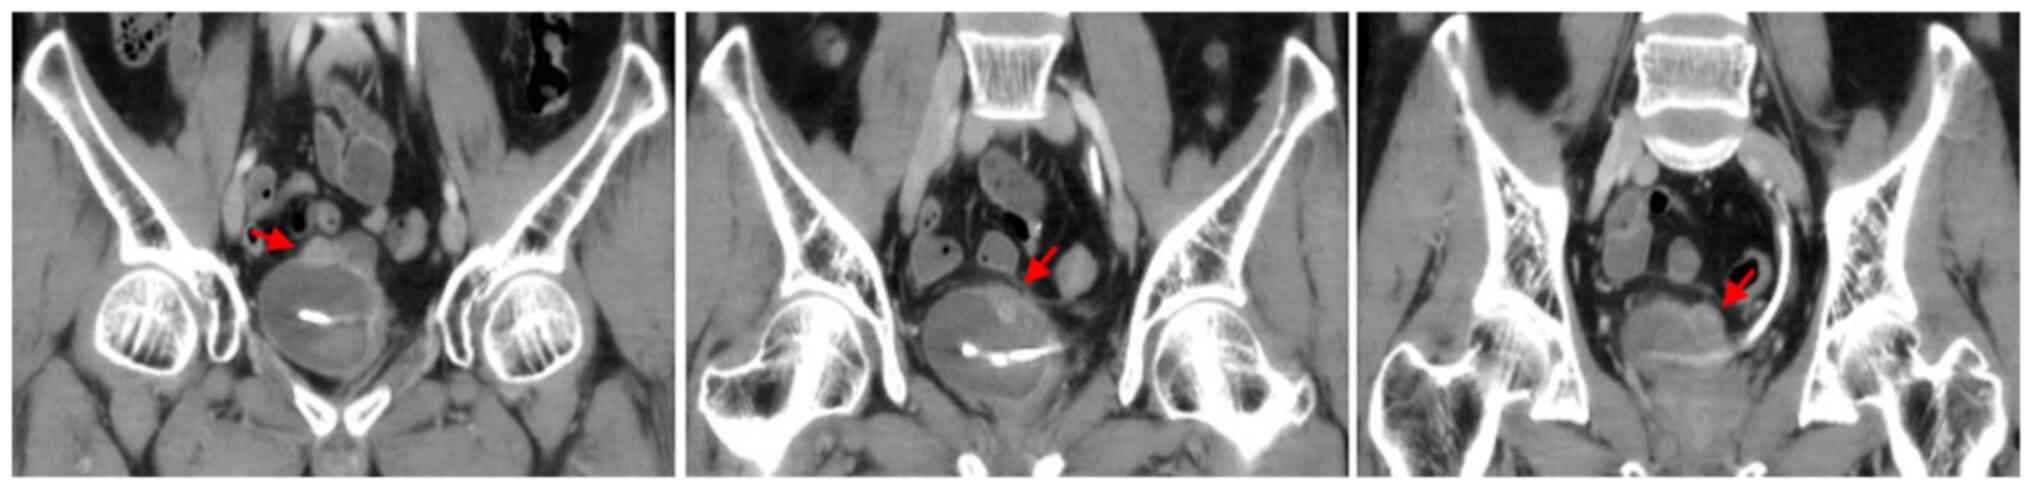

Figure 2

A 28-year-old man with gross hematuria, frequent urination, painful urination and irregular blood clot. (A) Unenhanced CT scan of the bladder showed a polypoid soft-tissue mass with an exophytic growth pattern on the superior wall, with homogeneous density. (B and C) Contrast-enhanced CT scans revealed ring enhancement on the margin of lesion and symmetrical change in the center of the lesion. CT, computed tomography.

The CT findings showed that 8 (89%) patients had one tumor and 1 (11%) patient had multiple tumors. The bladder IMT size ranged from 1.3x2.1 to 4.8x5.1 cm2. Tumors occurred in the posterior wall in 2 (22%) patients, 5 (30%) patients had tumors occurred in the superior wall, 1 (11%) patient had tumors occurred in the front wall, and 1 (11%) patient had tumor occurred in the left wall (Fig. 2, Fig. 3, Fig. 4 and Fig. 5). An endophytic growth pattern (Fig. 3) was identified in 4 (44%) patients, an exophytic growth pattern (Fig. 2) was observed in 2 (22%) patients, and a mixed growth pattern (Fig. 5) was revealed in 3 (33%) patients. The tumor manifests morphologically as either polypoid (n=5), or cauliflower-like (n=1) soft-tissue mass with a wide base in the cavity, or a limited thick-walled (n=3) in the bladder. The tumor margins were smooth (n=8) or lobulated (n=1) and the tumor boundaries were either clear (n=7) or ill-defined (n=2).

The unenhanced CT examination of the lesions revealed either low density (n=4), iso-density (n=3), or slightly high density (n=1), and density was either homogeneous (n=3) or heterogeneous (n=6). The enhanced CT examination of the lesions showed either ring-shaped (n=3) or heterogeneous (n=6), and the degree of enhancement was either significant (n=6), or moderate (n=3). The enhancement pattern was persistent (n=9). In addition, all polypoid and cauliflower-like soft-tissue masses showed a symmetrical change in the center of the lesion after enhancement on the CT image.